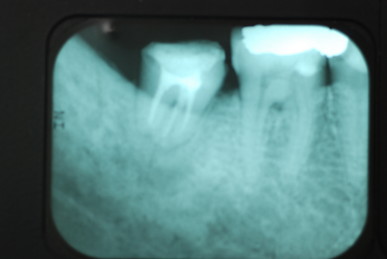

左下の一番奥の歯の治療がいい加減なようです。

左下の一番奥の歯の治療がいい加減なようです。しかし治療をしてみると滅菌しながら治療をすることの困難さを痛感しました。

三本ある根管の内、難しい手前の根幹の治療が為されていません。顎の骨に黒い影ができています。

根管治療終了です。

骨の部分は健康を回復しています。影がありません。治療が成功しています。

反対側の大臼歯には分岐部に深い虫歯と深い分岐部病変がありますが、虫歯の治療後は歯周病が酷いのに来られなくなりました。

上のレントゲンでも歯根の間に影があります。悪性の分岐部病変ですね。